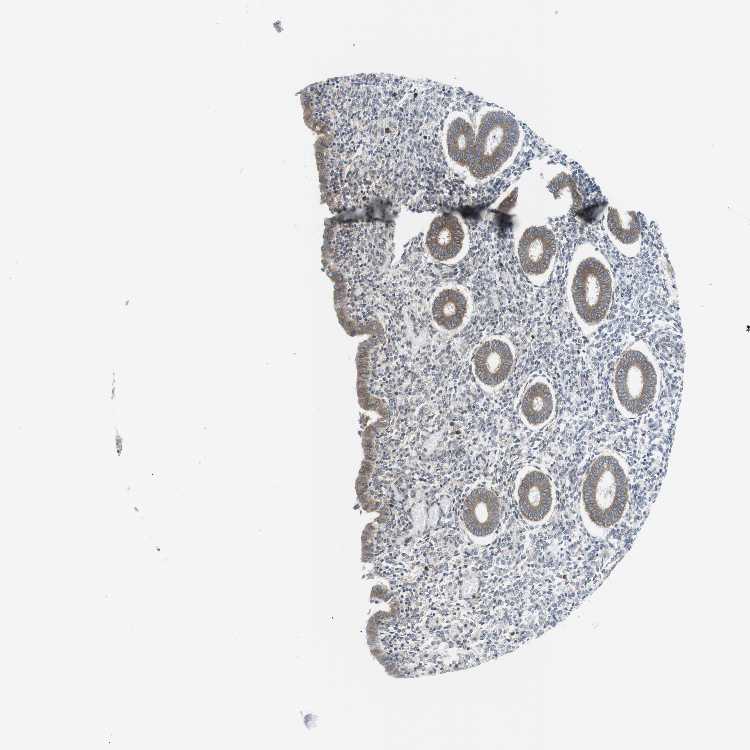

TISSUE PRIMARY DATA ENDOMETRIUM Show tissue menu

ENDOMETRIUM 1 - Antibody stainingi

Antibody staining in the annotated cell types in the current human tissue is reported as not detected, low, medium, or high, based on conventional immunohistochemistry profiling in selected tissues. This score is based on the combination of the staining intensity and fraction of stained cells.

Each image is clickable and will lead to virtual microscopy that enables deeper exploration of all samples and also displays staining intensity scores, fraction scores and subcellular localization as well as patient and tissue information for each sample.

Antibody HPA015242Antibody HPA015968

Cells in endometrial stroma Not detectedNot detected

Glandular cells MediumMedium

ENDOMETRIUM 2 - Antibody stainingi

Glandular cells HighLow